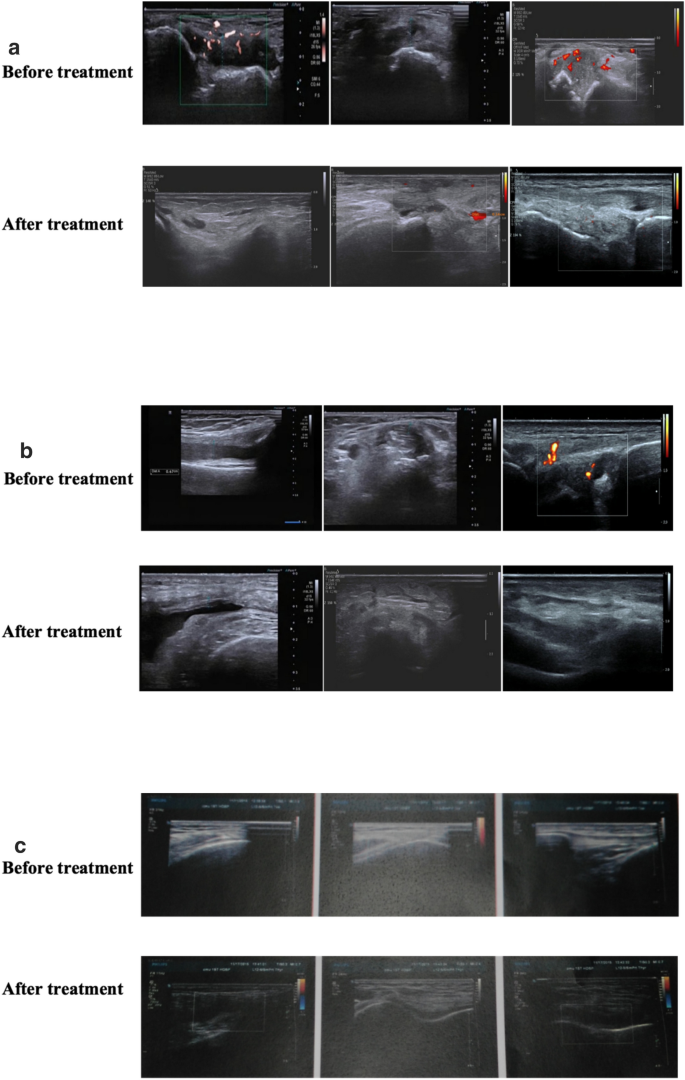

Comparison of change in CRP level, UA level, and thickness of the synovium of target joints before and after the treatment in the three groups

Compared with pretreatment, CRP and blood UA levels in the control and treatment groups decreased significantly after the treatment (P < 0.05). Still, no statistically significant difference was observed among the three groups, as shown in Table 3. In terms of change in the thickness of the synovium of target joints after the treatment, a significant improvement was seen in the T2 group (P < 0.05), which was better than that in the control group (basic treatment group), as shown in Table 4 and Fig. 5.

Ultrasound has the characteristics of easy operation, noninvasiveness, flexibility, and high sensitivity and hence provides vivid and visualized monitoring and assessment for patients with gout [44]. Therefore, it is widely applied in the diagnosis and evaluation of gouty arthritis. Synovium thickening was a typical manifestation of gout in the acute stage. In this study, a significant decline in the thickness of the synovium of joints was observed in the CQBG treatment group compared with the control group. In this study, the detection rate of double-track sign under ultrasound is not high. The reason may be that the patients in this study were in patients in a serious condition, most of them also had apparent gout stones and bone destruction. Hence, the sound attenuation affected the detection rate. At the same time, the double-track sign should be differentiated from calcium pyrophosphate deposition in the joint (also known as pseudogout).